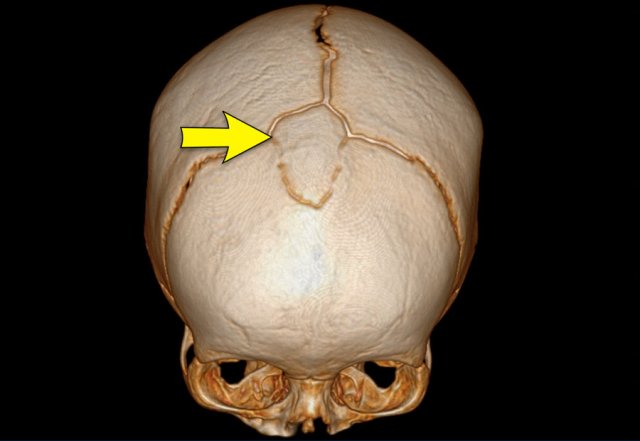

Images

Slight metopic ridge in a nine-month-old (arrow). Note that the scan was taken for a different purpose.

Metopic ridge can be clinically diagnosed and should not be imaged.

The anterior fontanelle has already closed but apart from the metopic suture, the other sutures are still open.